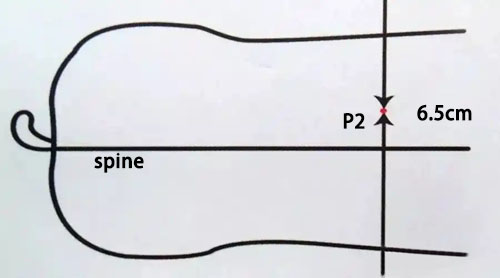

Locate the measurement point—usually the P2 position, which is located approximately 6–7 cm off the midline of the pig’s back at the level of the last rib.

Pig back fat eye muscle detection position